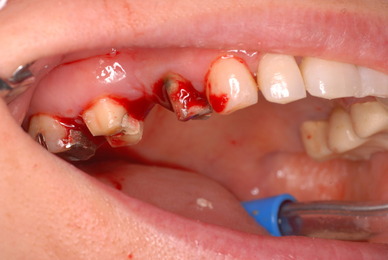

お口の中から差し歯、入れ歯、詰め物を追放しましょう!

口の中の病気を治し、病気を興さない医療を目指します。

予防に精進いたしましょう!安全な矯正、美容を目指しましょう!